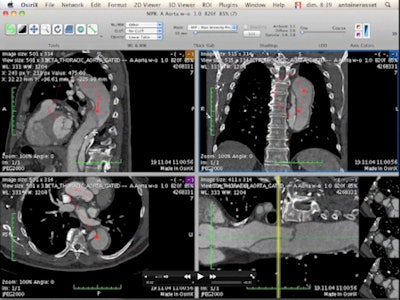

![]() |

| Quantitative analysis of hybrid PET/CT images of a head and neck tumor, using OsiriX open-source software. (Provided by Prof. Osman Ratib) |